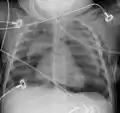

Pneumomediastinum is uncommon and occurs when air leaks into the mediastinum. The diagnosis can be confirmed via chest X-ray showing a radiolucent outline around the heart and mediastinum or via CT scanning of the thorax.